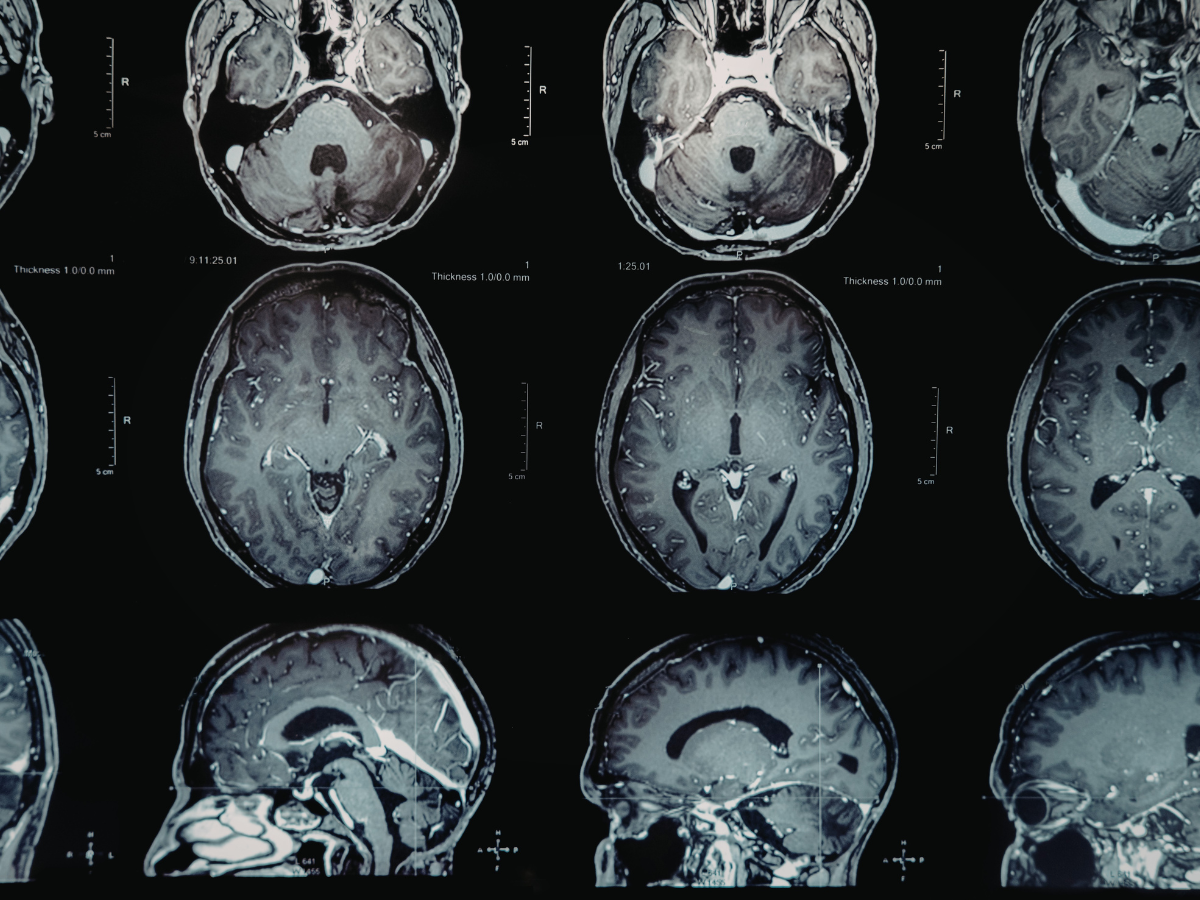

Published recently in Nature Medicine, this study represents the largest brain-imaging meta-analysis in the history of psychedelic research. By combining 11 datasets from across five countries and analyzing more than 500 brain scans from 267 individuals, researchers have moved the industry away from small-scale observations toward a definitive, large-scale evidence base.

The most striking hallmark identified in the research is a massive increase in “cross-talk” between brain systems. Under the influence of these compounds, higher-level thinking networks begin communicating intensely with more primitive regions responsible for sensation and vision.

While previous, smaller studies suggested that certain brain networks simply “disintegrated” during a trip, this larger data set clarifies the reality: the brain isn’t just breaking down—it is communicating in a way that is vastly more interconnected and “unleashed” than its normal state. This “excessive cross-talk” is believed to be the engine behind the profound shifts in perspective and sensory experiences reported by clinical trial participants.